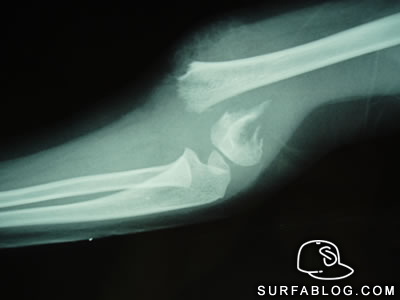

Un'iniezione e l'osso danneggiato torna come nuovo. Un passo avanti possibile grazie ad un nuovo materiale composito iniettabile, utilizzabile per il trattamento delle fratture e delle patologie del sistema scheletrico, brevettato dall'Imcb-Cnr di Napoli e Finceramica. Il dispositivo, costituito da un polimero sintetico e materiale bioceramico riassorbibile è iniettabile mediante tecniche chirurgiche o vie d'accesso anatomiche mini invasive. La solidificazione avviene in pochi minuti, compatibilmente con i tempi della chirurgia, colmando il difetto osseo e stimolando la rigenerazione. Una volta riassorbito, infatti, il materiale promuove il processo di rigenerazione del tessuto osseo, riparando così fratture che presentano tempi lunghi di recupero o riempiendo cavità dovute a interventi chirurgici demolitivi.